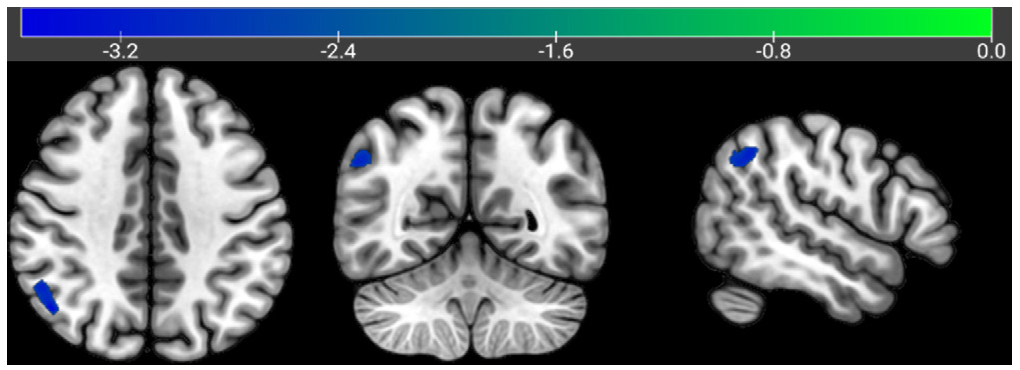

Among the 66 patients, 42 had mild-to-moderate AD, and 24 had severe AD. Among the mild-to-moderate group, 16 had a history of alcohol consumption and 26 did not. Among patients with mild to moderate AD, the proportion of males with a history of alcohol consumption and the proportion of those with a history of smoking were higher than those without such histories (P<0.05) . Among the 24 patients with severe AD, 9 had a history of alcohol consumption and 15 did not. Among the patients with severe AD, the proportion of males with a history of alcohol consumption and the proportion of those with a history of smoking were higher than those without a history of alcohol consumption (P<0.05) . In patients with mild to moderate AD, the GMV of the right angular gyrus in those without a history of alcohol consumption was lower than that in those with a history of alcohol consumption (t=-3.698, P<0.05) . In patients with severe AD who had a history of alcohol consumption, the GMV of the left superior temporal gyrus was lower than that of those without a history of alcohol consumption (t=5.774, P<0.05) .

A history of alcohol consumption appears to significantly influence patterns of gray matter atrophy in AD patients. In mild-to-moderate AD, drinking may be associated with attenuated atrophy in the right angular gyrus, whereas in severe AD, it is linked to increased atrophy in the left superior temporal gyrus. These findings suggest a dual role of alcohol consumption in the progression of AD.